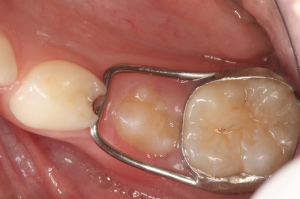

Na tentativa de evitar ou amenizar os possíveis problemas causados pela perda precoce de um molar decíduo, são instalados dispositivos mantenedores de espaço, como o banda-alça, arco lingual, arco transpalatino e botão de Nance, cada qual com suas indicações.

Quando falamos sobre perda precoce de molares decíduos inferiores, os aparelhos mais utilizados são o arco lingual, na situação de perdas múltiplas, e o banda-alça em casos de perda unitária. As principais vantagens desses dispositivos são a possibilidade de bandagem tanto em molares permanentes como decíduos, a facilidade para a instalação e remoção, baixo custo e não dependência da colaboração do paciente, pois são fixos.